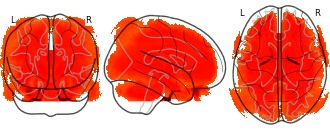

"name": "VBM_HeterogeneityMap",

"description": "Abnormal gray matter in BPD. Brain regions with significant heterogeneity (i.e. between-study variance) in the comparison of patients with BPD and healthy controls. Results are thresholded at at p<.005 & k>20. Note: Results are based on meta-analysis of group comparisons. Note2: Results were updated (see Erratum for this publication)",

"add_date": "2016-01-21T18:23:32.131003+01:00",